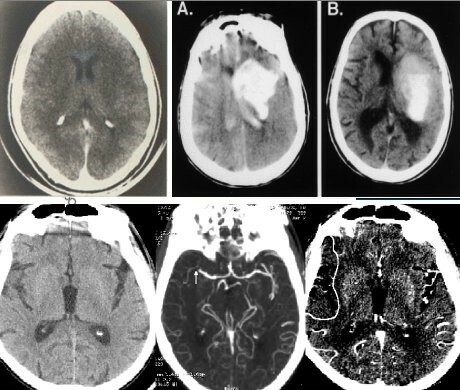

• Houndsfield y Cormack

Houndsfield y Cormack

La Tomografía Axial Computarizada (TAC) hizo que ellos fueran merecedores del Premio Nobel al permitir por primera vez, la visualización de lesiones a partir de imágenes del interior del cráneo.